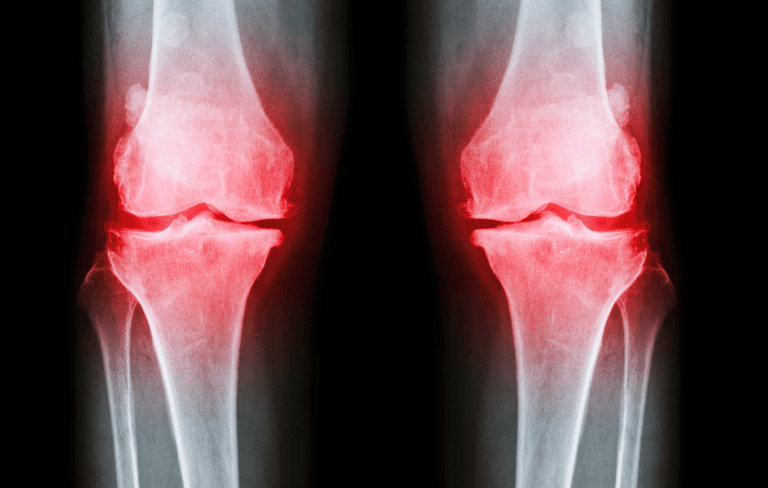

OA, the most common form of arthritis, affects millions of lives, causing pain, stiffness, and limiting joint motion.

Imagine a life where every step feels like a jab of pain, where once-favorite activities become daunting challenges. Osteoarthritis (OA) threatened to rewrite one client's story, but they refused to let it define them. Instead, they embarked on a journey to discover how running could coexist with this degenerative condition, defying the odds and emerging stronger.

However, people with OA may still experience symptom flares in the knee joints due to running.